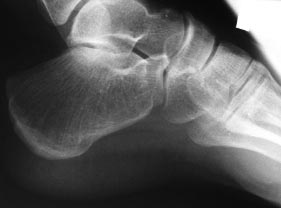

Похоже на болезнь Хаглунда. Как раз, чаще всего у молодых женщин бывает. Нужно рентгенограммы пяток в боковой проекции посмотреть и фотографии пяток сзади. Если Хаглунд, то основная задача лечения - удаление костной выпуклости под ахилловым сухожилием. Делать это можно открыто, чрескожно, эндоскопически. Позадиахилловую слизистую сумку можно не иссекать. Ахиллово сухожилие постараться травмировать минимально. Но сначала нужно все-таки уточнить диагноз.

Спасибо всем, кто принимает участие в обсуждении случая. Досылаю рентгенограммы и МРТ. Хотелось-бы уточнить объем резекции пяточных костей.

Юрий Алексеевич Булахтин

Камчатский Военно-морской госпиталь